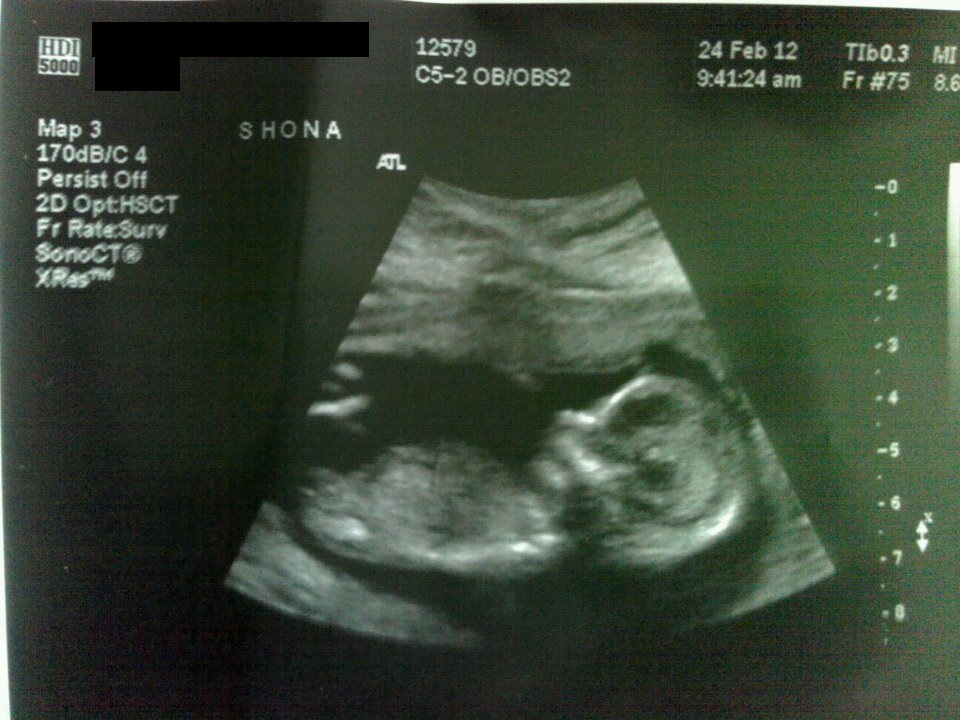

Im going to guess Girl.

I think girl :)

I'm guessing girl as well.

I think it's a girl too.

i think girl hun ,

Don't think we see the whole nub but I guess girl.

I don't think we're seeing the whole nub. Good luck.